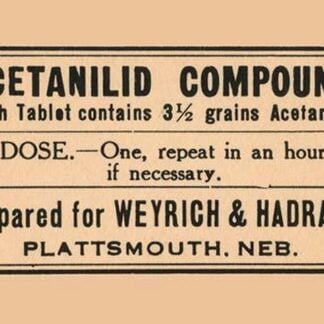

Acetanild Compound

Price range: $21.99 through $285.99 Select options This product has multiple variants. The options may be chosen on the product page -